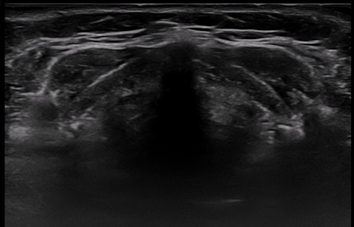

그림 3 (A)

그림 3 (B)그림 3. 동적구역 조절(Dynamic Range Control). 동적구역을 증가시키면 부드럽지만 대조도가 저하된 영상을 얻게되고(A), 동적구역을 저하시키면 거칠지만 대조도가 증가된 영상을 얻을 수 있다(B).